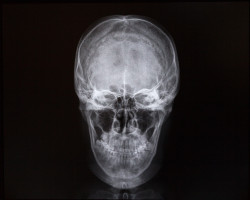

X-rays of skull and internal cavity. MedicineA woman has filed a Mirena lawsuit after the intrauterine birth control system caused her to develop pseudotumor cerebri.

A neurologist soon diagnosed her with pseudotumor cerebri, an alleged complication of her Mirena implant. Pseudotumor cerebri, also known as intracranial hypertension, is a condition that occurs when a patient’s cerebrospinal fluid becomes elevated. Normally, the fluid is released and absorbed by the body.

Pseudotumor cerebri is so named because the pressure inside the skull acts like a tumor but is not a real tumor. The pressure is caused by excess cerebrospinal fluid that has not properly been absorbed by the body. Increased pressure from this fluid can cause migraine-type headaches with visual disturbances because of increased pressure on the optic nerve.

Pseudotumor cerebri is most often diagnosed after a lumbar puncture is performed, allowing the cerebrospinal fluid to be evaluated. When infection or inflammation in the fluid is ruled out and the fluid appears normal, pseudotumor cerebri is diagnosed as the problem.

Anywhere from five to 15 millimeters of mercury is considered normal intracranial pressure.

According to the Mirena lawsuit, Alfreda “underwent a diagnostic lumbar puncture to evaluate increased cranial pressure, with an opening pressure of 25 cm” in November 2017.